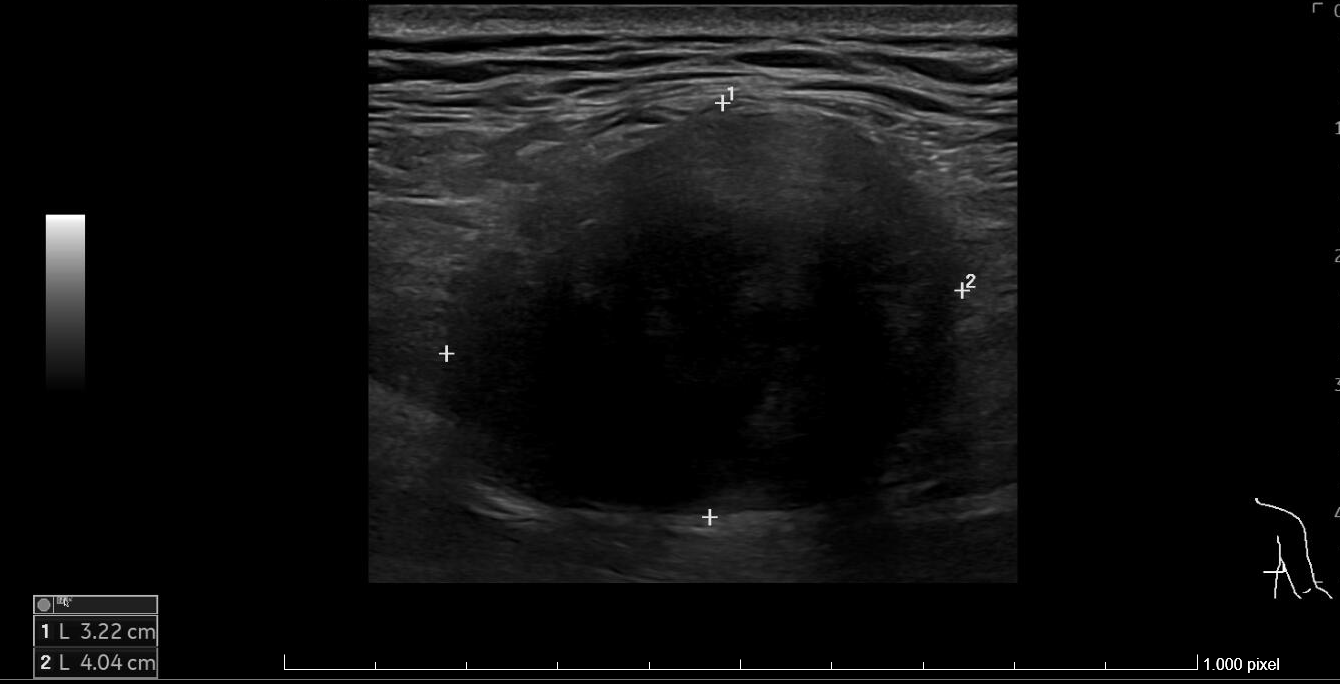

Ecografía: en el tercio medio y posterolateral de la pared torácica derecha, se observa una tumoración sólida, con densidad de partes blandas a nivel más craneal y un componente graso heterogéneo en el polo inferior, de aproximadamente 40 x 32 x 53 mm (transversal-AP-craneocaudal) que presenta pequeños vasos en su interior. Se sitúa en la en el plano muscular superficial, aproximadamente a 7 mm de profundidad respecto a la piel.